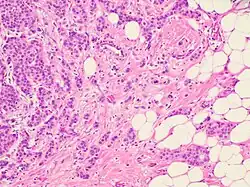

Krakhmal et al. have studied the features of breast cancer progression depending on intratumoral heterogeneity. Attention has been paid to the phenotypic diversity of the primary tumor in invasive carcinoma of no special type, which accounts for the bulk (80%) of all histological types of breast cancer.[2]

Despite the structural diversity of the primary breast tumor, five main types of morphological structures can be distinguished: alveolar, trabecular, tubular and solid structures, and discrete groups of tumor cells. The alveolar structures are tumor cell clusters of round or slightly irregular shape. The morphology of the cells that form this type of structures varies from small cells with moderate cytoplasm and round nuclei to large cells with hyperchromatic nuclei of irregular shape and moderate cytoplasm. The trabecular structures are either short, linear associations formed by a single row of small, rather monomorphic cells or wide cell clusters consisting of two rows of medium-sized cells with moderate cytoplasm and round normochromic or hyperchromatic nuclei. The tubular structures are formed by a single or two rows of rather monomorphic cells with round normochromic nuclei. The solid structures are fields of various sizes and shapes, consisting of either small cells with moderate cytoplasm and monomorphic nuclei or large cells with abundant cytoplasm and polymorphic nuclei. Discrete groups of cells occur in the form of clusters of one to four cells with variable morphologies.[2]

The different morphological structures of breast tumors correspond to certain types of invasion. Therefore, alveolar, trabecular, and solid structures that are characterized by the presence of cell-cell contacts may be referred to morphological manifestations of collective migration, while discrete groups of tumor cells may be referred to manifestations of individual migration. The first batch of data obtained in a study of the expression of cell adhesion genes confirms this hypothesis. For example, there was a decrease in the activity of the genes of cadherins, which are responsible for cell-cell contacts, in the order: solid – alveolar and trabecular structures – discrete groups of tumor cells. In this case, the number of expressed genes of integrins involved in the adhesion of tumor cells to the extracellular matrix was reduced in the order: solid and alveolar – trabecular structures – discrete groups of tumor cells.[2]